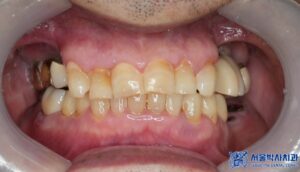

이번에 저희 서울박사치과를 찾아주신 환자분께서는

기존에 다른 치과에서 임플란트 치료를

받으셨었지만, 기존 임플란트와 보철물이

파절되면서 다시 진단을 받아보고자

저희 치과에 내원하셨습니다.

우선, 환자분의 상악 오른쪽 어금니들은

치주 염증이 심한 상태로,

기존에 받으셨던 보철물 아래로 염증이

심하게 퍼져 제거가 필요한 상태였습니다.

뿐만 아니라, 상하좌우 맨 안쪽 어금니들의

잇몸과 뼈 상태가 많이 악화되어 있어

보존이 어려운 상황이었기에

각각 발치도 진행되어야 했습니다.

치료 마무리 후 사진입니다.

최종 보철물 세팅 이후 환자분께서는 불편함도 없었고,

교합 체크를 위해 다시 내원하셨을 때도

“음식 씹을 때 너무 편하고, 교합도 잘 맞는다”고

만족해하셨습니다.